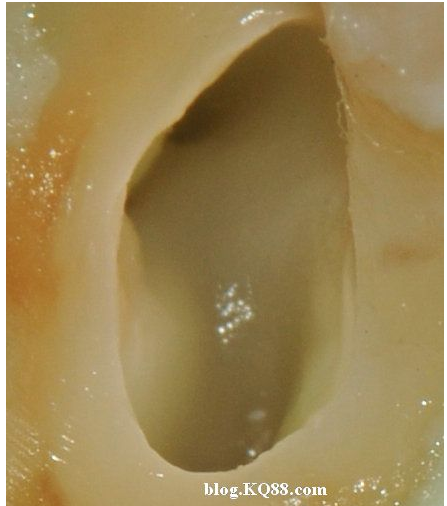

下邊這張圖可以看出氣泡明顯少了,說明次氯酸鈉的溶解速度變慢了。

棉球吸除2%的次氯酸鈉,可以看到牙髓明顯的被溶解掉一部分